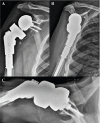

Case presentation: We report a case of a 70-year-old male with periosteal chondrosarcoma of the proximal humerus who underwent margin-negative resection and reverse total shoulder endoprosthetic reconstruction that was complicated by glenosphere dissociation sustained from falling onto a hyperflexed arm. Successful revision arthroplasty was performed.

Conclusion: Enhancing glenohumeral joint stability after wide resection of the proximal humerus is important to address rotator cuff insufficiency. The greater levering effect of a longer humeral prosthesis used to increase soft tissue tension may also increase the risk of glenosphere dissociation secondary to trauma. Proper soft-tissue tensioning and surgical technique are critical.